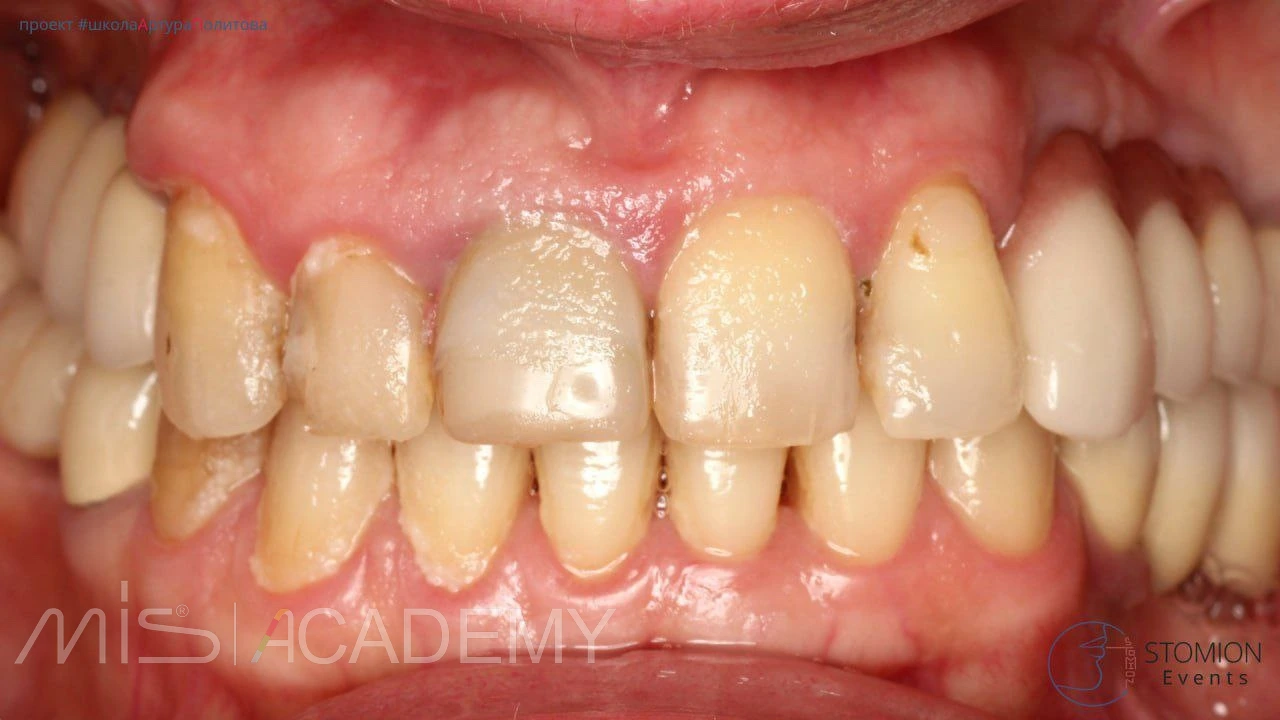

Атравматичное удаление зуба 1.1 с использованием системы Benex. Тип лунки — I (интактная).

— Выполнена одномоментная установка имплантата MIS C1 3,75 × 13 мм с коннектом 3 мм. Зазор более 2 мм.

— Проведена аугментация материалом Bio-Oss Collagen.

— Произведён забор СТТ с бугра верхней челюсти.

— Вестибулярно, в области свободного десневого края и сформированного кармана по типу «конверта», уложен деэпителизированный соединительнотканный трансплантат с целью профилактики коллапса мягких тканей.

— С нёбной стороны использован трансплантат с сохранённой эпителиальной полоской для компенсации дефицита мягких тканей.

— Выполнена немедленная нагрузка с использованием позиционера.